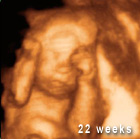

In Oregon, The House Judiciary Committee held an informational session on House Bill 3512, which would prohibit abortions once a pregnancy is in its 20th week, barring a medical emergency threatening the mother’s life.